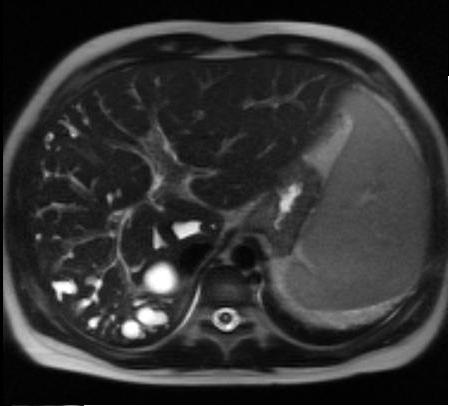

Image TDM , coupe axiale d'une

kyste choledoque de type III . Aspect du

lesion hypodense ovalaire et n'a pas de rehaussement

de contrast intraveineuse |

|

Image radiologique de meme

cas en coupe coronal ( frontal ) .. Kyste du canal

choledoque de type III |